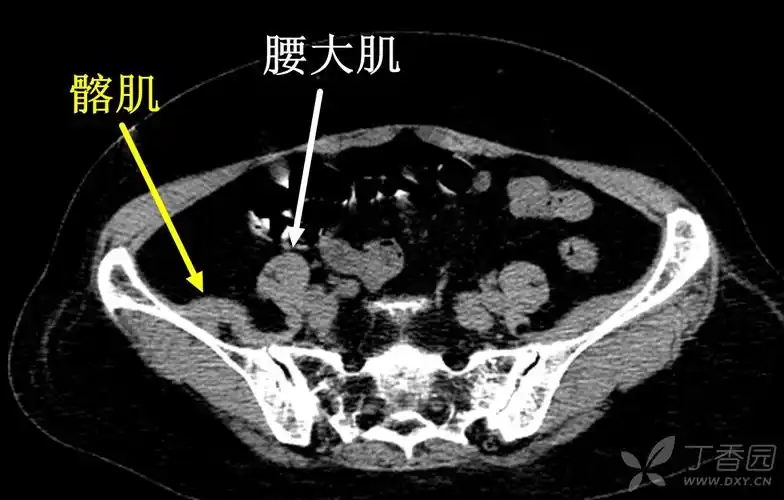

骨盆,臀部肌肉囊肿,一个盆腔,髋关节不适,疼痛的少见原因 [精华]